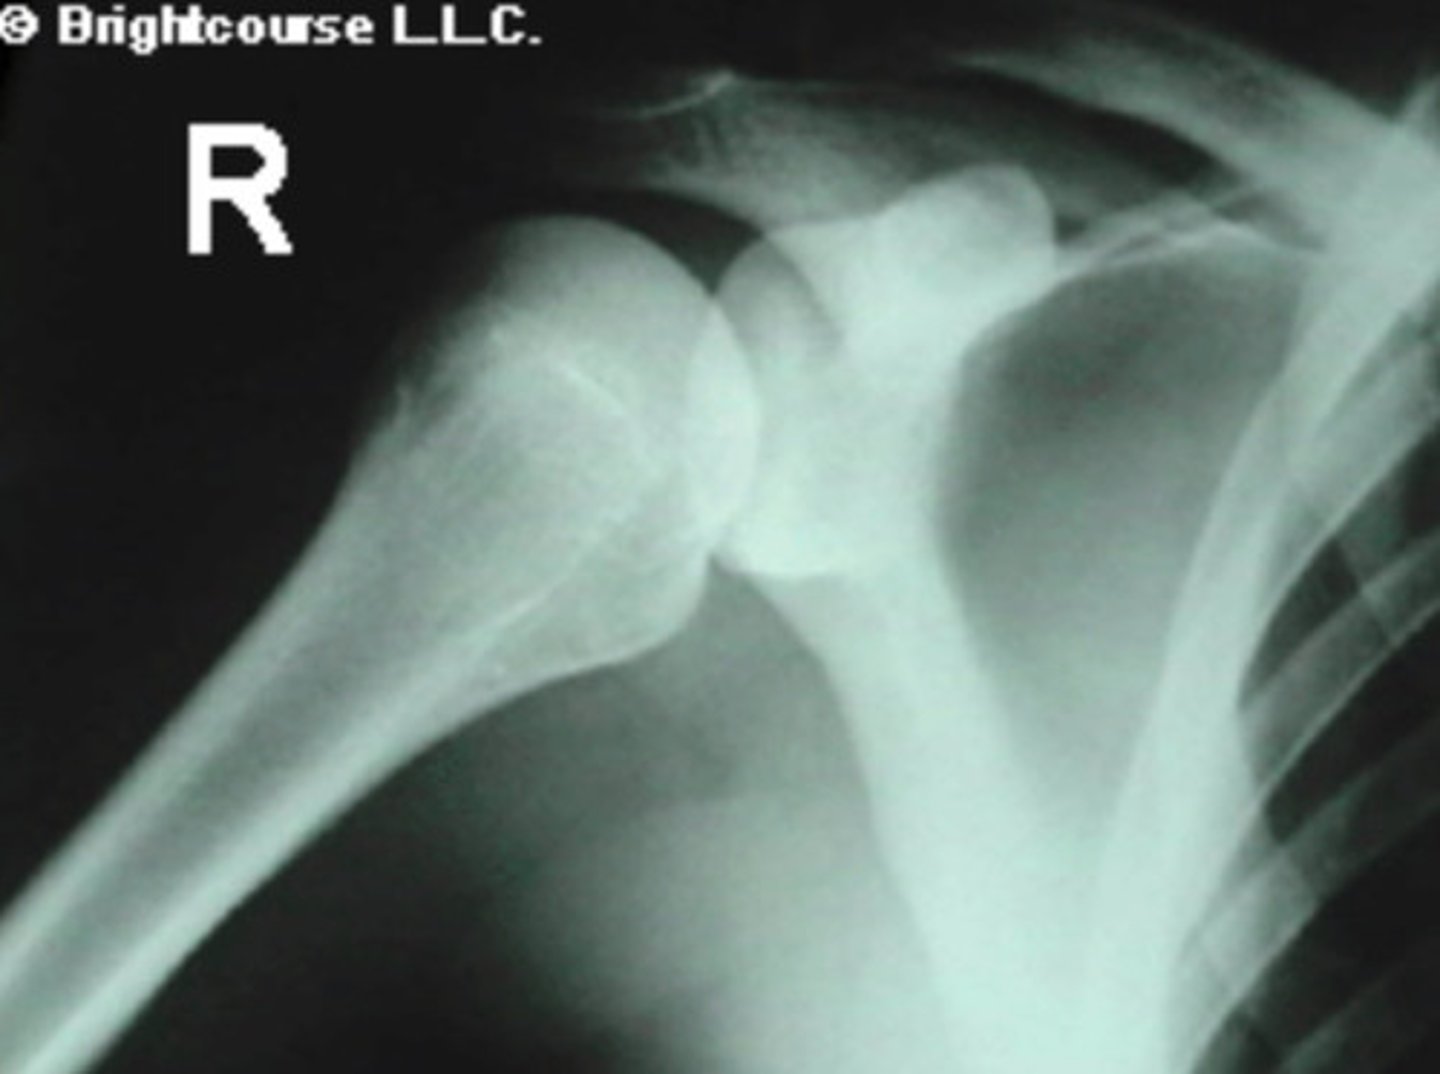

AP Internal Rotation of Shoulder

What is the name of the radiographic projection seen here?